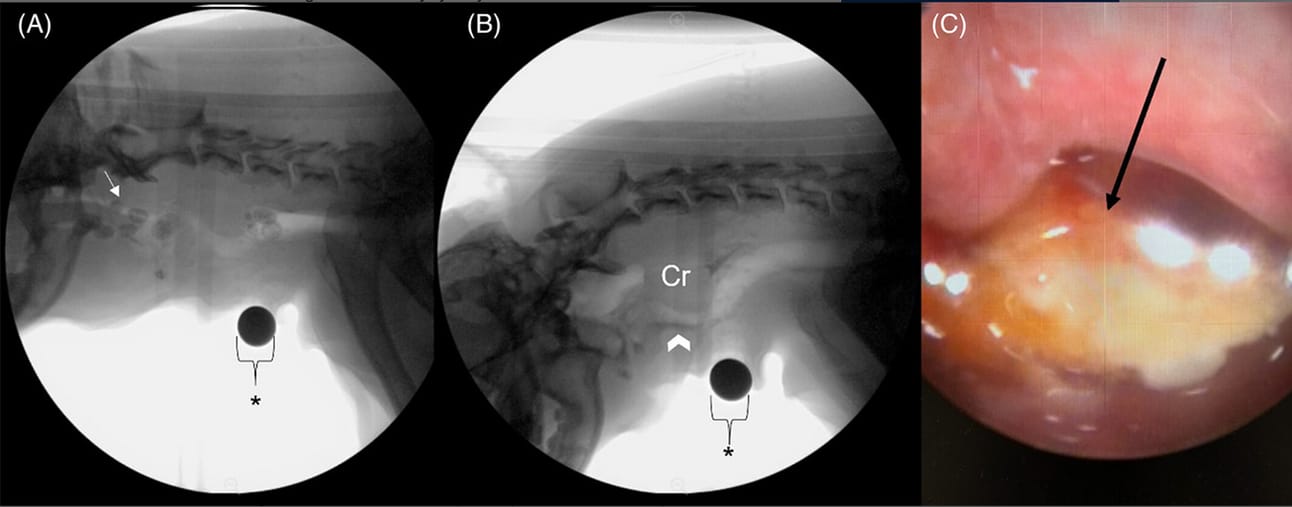

(A-C) A still VFSS image from a 13-year-old MC Boston Terrier diagnosed with cricopharyngeal achalasia after being evaluated for chronic cough and mucopurulent nasal discharge. (A) The dog is freely consuming a kibble consistency. Kibble is seen above the soft palate following pharyngeal swallow demonstrating nasopharyngeal reflux (white arrow). (B) The dog is freely consuming a liquid consistency. A hypertrophied cricopharyngeus muscle (Cr) demonstrates a classic “thumbprint” pattern. Macroaspiration is observed with material entering the cervical trachea (arrowhead). (C) An image from a retroflexed choanal examination of the nasopharynx identified a foreign body (carrot; black arrow). A 1 cm size marker is denoted by the asterisk (*). The image from the choanal examination was provided by Dr. Vientos-Plotts, University of Missouri.